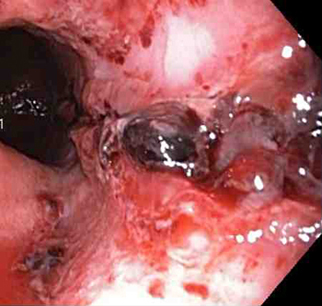

coágulo aderente sem sangramento

Do acervo de Juan Carlos Munoz, MD, University of Florida